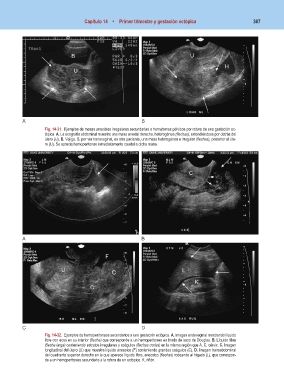

Fig. 14-31. Ejemplos de masas anexiales irregulares secundarias a hematomas pélvicos por rotura de una gestación ec-

tópica. A. La ecografía abdominal muestra una masa anexial derecha, heterogénea (flechas), extendiéndose por detrás del

útero (U). B. Vejiga. B, por vía transvaginal, en otra paciente, una masa heterogénea e irregular (flechas), posterior al úte-

ro (U). Se aprecia hemoperitoneo inmediatamente caudal a dicha masa.

Fig. 14-32. Ejemplos de hemoperitoneos secundarios a una gestación ectópica. A. Imagen endovaginal mostrando líquido

libre con ecos en su interior (flecha) que corresponde a un hemoperitoneo en fondo de saco de Douglas. B. Líquido libre

(flecha larga) conteniendo estratos irregulares y coágulos (flechas cortas) en la misma región que A. C, cérvix. C. Imagen

longitudinal del útero (U) que muestra líquido anecoico (F) conteniendo grandes coágulos (C). D. Imagen transabdominal

del cuadrante superior derecho en la que aparece líquido libre, anecoico (flechas) rodeando al hígado (L), que correspon-

de a un hemoperitoneo secundario a la rotura de un ectópico. K, riñón.